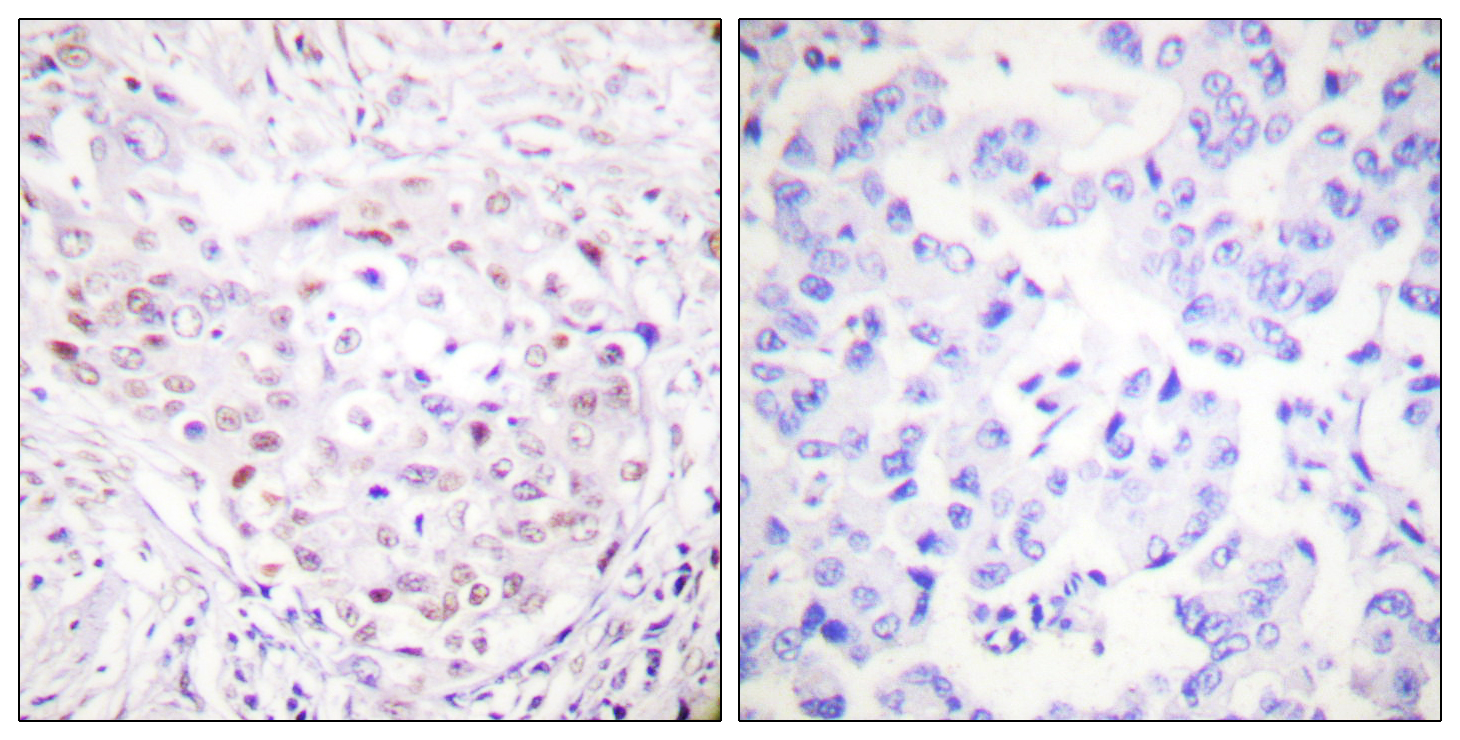

分类: 科研抗体货号: P23177别名: MTB; CAPG2; LUZP5; CAP-G2; hCAP-G2应用: IHC反应种属: Human